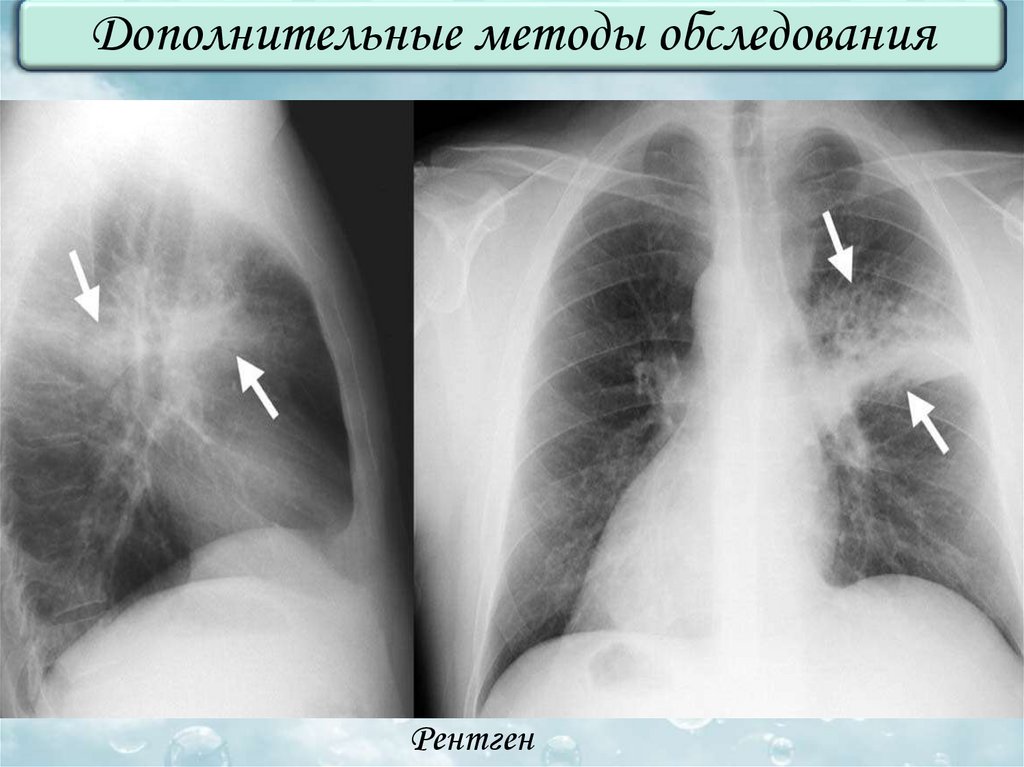

Дополнительные методы обследования

Рентген